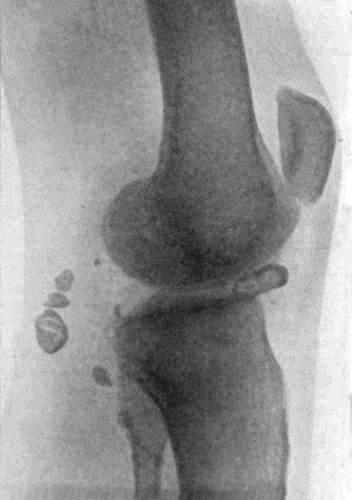

| 154. | Osseous Ankylosis of Femur and Tibia | 503 |

| 155. | Osseous Ankylosis of Knee | 504 |

| 162. | Bones of Knee in Charcot's Disease | 533 |

| 163. | Charcot's Disease of Left Knee | 534 |